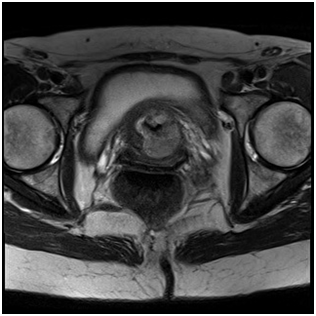

A 54-year old white woman, without significant past medical history other than menopause since 2years ago presented with post coital hematuria and also she had urinary tract infections (UTIs), documented by urine cultures (Proteus Mirabillis). No other associated symptoms. She received antibiotic therapy with quinolones. The urine cytology was negative. The assessment by the Gynecology service was normal. The renal ultrasound (US) Each kidney was normal, preserved cortico medullary differentiation and without dilated collecting systems. There was irregularity zone in the mucosa close to bladder neck, measuring 1x0.5cm. Cystoscopy revealed an edematous and erythematosus lesion of 1x1.5cm in the posterior wall of the bladder neck that extended into the urethra. In pelvic magnetic resonance imaging (MRI) a pelvic mass was evident measuring 35x38x47mm, widening the bladder neck at this level, nonspecific inguinal adenopathies and a left iliac node with malignancy aspect.

Figure 3 Initial pelvic MRI

Radical cystourethrectomy was performed with bilateral pelvic lymph node (extense iliac region) dissection (Figure 4) and anterior vaginal wall excision (vaginoplasty) followed by ileal urinary diversion (Bricker type). Ureteral end edges were sent to frozen biopsy and the results were negative. The specimen’s pathology was “adenocarcinoma with clear cell areas and focus of papillary, located in the trigone region, affecting the peri vesical tissues without infiltrating the muscular layer of the vagina (pT4a). Bilateral pelvic lymph nodes were free of tumor (12 nodes in the left side and 14 in the right side), like the rest of organs. Neoplasia stage: pT4a pN0 pM0”.

Figure 4 Initial pelvic MRI.